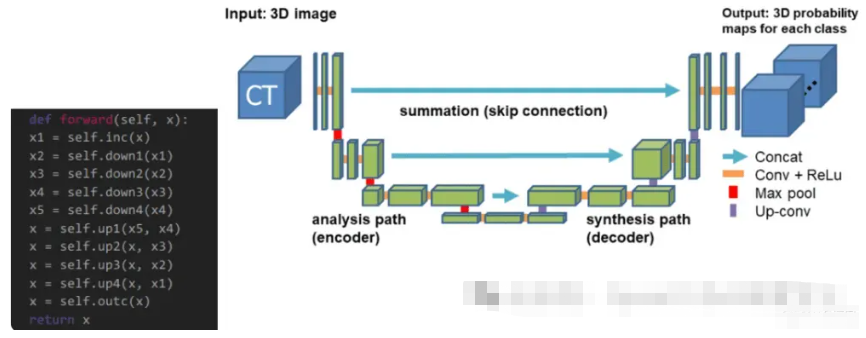

【1】您能解释一下什么是UNet架构以及它是如何使用的吗?

UNet架构是专门为图像分割任务设计的深度学习模型。Olaf Ronneberger 等人在论文“U-Net:用于生物医学图像分割的卷积网络”中介绍了它。

UNet架构由两部分组成:收缩路径和扩展路径。收缩路径是一系列卷积层和最大池化层,用于对输入图像进行下采样并提取特征。扩展路径是一系列卷积层和上采样层,它们对收缩路径中的特征图进行上采样,并将它们与输入图像中的特征组合以生成最终的分割图。

UNet 架构通常在大型带注释图像数据集上进行端到端训练,以预测每个图像的像素级分割图。可以训练模型来分割单个类别或多个类别,具体取决于具体任务。

UNet 广泛应用于各种图像分割任务,例如医学图像分割、卫星图像分析和自动驾驶车辆中的目标检测。它以其处理高分辨率图像和生成准确分割图的能力而闻名。

【2】UNet架构的主要组成部分是什么,它们如何协同工作?

UNet架构的主要组成部分是收缩路径、扩展路径和跳跃连接。

收缩路径是一系列卷积层和最大池化层,它们对输入图像进行下采样并从中提取特征。卷积层将一组滤波器应用于输入图像并生成特征图,而最大池化层通过在像素窗口内获取最大值来对特征图进行下采样。

最终的分割图是通过对收缩路径中的特征图进行上采样并将其与扩展路径中输入图像的特征相结合而创建的,扩展路径是一系列卷积层和上采样层。卷积层将一系列滤波器应用于上采样的特征图以创建最终的分割图。相反,上采样层通过重复像素窗口内的值来提高特征图的空间分辨率。

这些连接(称为“跳跃连接”)绕过扩展路径中的一个或多个级别,并将它们链接到收缩路径中的相应层。它们使输入图像中的高级和低级信息能够合并到模型中,从而提高分割图的精度。